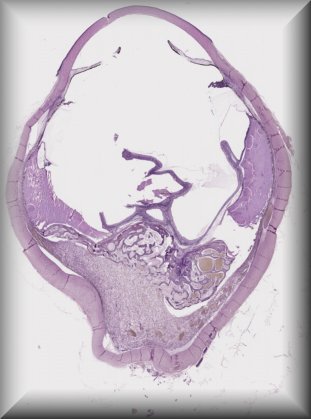

Patricia Chévez Barrios (Houston): 2 year-old-boy with history of group D unilateral retinoblastoma s/p systemic chemotherapy, cryotherapy and intravirteous chemotherapy. Enucleated for progressive disease. |